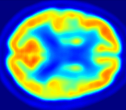

| MRI | PET | U-PET | U-PET (no att.) | pix2pix |

4.0.2 Qualitative Results

Looking at sample synthetic PET images in Fig. 3, it can be seen that all of the models are able to make reasonable predictions. The outputs of the U-PET and U-PET (no att.) look very similar and are smoothed compared to the input. The pix2pix predicts more details, which seem to be important for the discriminator. However, even though this model has finer predictions, the intensity values are worse compared to the U-PET and U-PET (no att.) as seen in Fig. 2; an example is given in Fig. 3 in the second row.

From a clinical perspective, the synthetic generated PET show a smoother version of the real PET images but keep the same pattern of FDG uptake, especially, hypometabolism in the respective brain areas. This backs up our hypothesis, that MRI contains information that correlates with the functional information of PET images. Moreover, the synthetic PET could be used as complementary visualization for physicians beyond the task of classification.